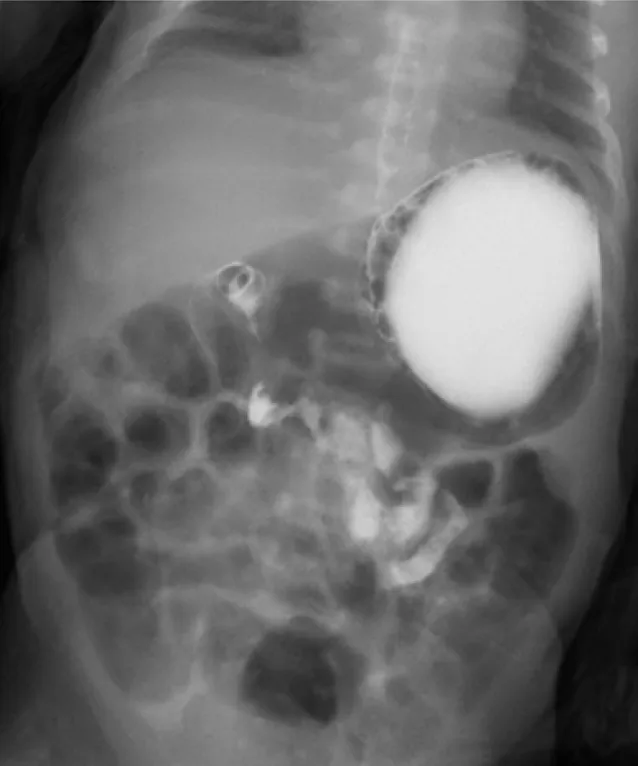

【115-1 醫學(四) 第74題】出生兩天大的女嬰因嘔吐不止就醫,接受上消化道攝影結果如圖示,下列何者為最可能之診斷?